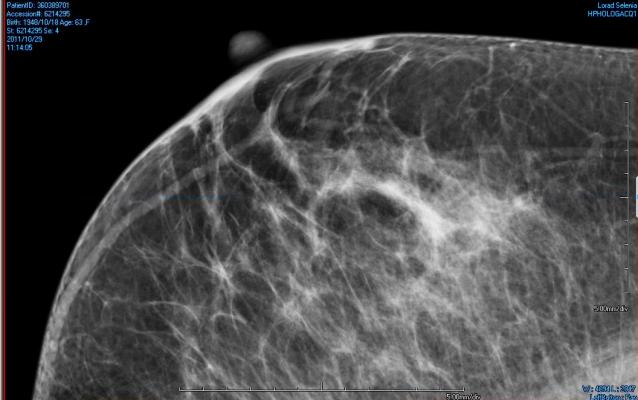

What Does Cancer Look Like On Mammogram : Mammography 3d Mammography Tomosynthesis Densebreast Info Inc / The rate of breast cancers discovered as dcis is thought to be increasing, but this is partially a testament to the effectiveness of mammographic breast cancer screening programs.ductal carcinoma in situ represents up to 30% of all new cases of breast cancer discovered by breast cancer screening.. Regular mammograms are the best tests doctors have to find breast cancer early, sometimes up to three years before it can be felt. In this mammogram image, the breast calcifications are in ductal patterns. Any area that does not look like normal tissue is a possible cause for concern. Calcifications are tiny flecks of calcium — like grains of salt — in the soft tissue of the breast that can sometimes indicate the presence of an early breast cancer. Any area that does not look like normal tissue is a possible cause for concern.

Abnormalities such as cancerous tumors usually appear brighter because they are denser. In this mammogram image, the breast calcifications are in ductal patterns. Dr sarah jarvis mbeif a mammogram is abnormal, further tests will be needed. Breast cancer and some noncancerous (benign) breast conditions can appear white on a mammogram. You may notice dimpling or pitting, and the skin on your breast.

Invasive breast cancer can appear as a white patch or mass on a mammogram. The tumor cells don't stay within the clear borders of the mass, but instead invade the nearby breast tissue. You may notice dimpling or pitting, and the skin on your breast. A rash isn't the only visual symptom of inflammatory breast cancer. Regular mammograms are the best tests doctors have to find breast cancer early. In a normal breast, a mammogram shows normal skin dark grey fat and lighter grey breast tissue. According to the american cancer society (acs), the most common sign of breast cancer is a new lump or mass in the breast. How can mammograms be used? Cancers may be seen as masses (like a ball, but usually with an irregular shape), areas of asymmetry that resemble normal tissue, calcifications (white specks), and/or areas of architectural distortion (imagine the puckering caused by pulling a thread in a piece of fabric). In this mammogram image, the breast calcifications are in ductal patterns. Healthy mammograms can still vary in appearance. It is important to bear in mind that most women who are asked to come back after. Any area that does not look like normal tissue is a possible cause for concern.

Ibc symptoms are caused by cancer cells blocking lymph vessels in the skin causing the breast to look inflamed. symptoms include breast swelling, purple or red color of the skin, and dimpling or thickening of the skin of the breast so that it may look and feel like an orange peel. What does cancer look like on a mammogram? Cancers may be seen as masses (like a ball, but usually with an irregular shape), areas of asymmetry that resemble normal tissue, calcifications (white specks), and/or areas of architectural distortion (imagine the puckering caused by pulling a thread in a piece of fabric). Tumors may be benign or cancerous. According to the american cancer society (acs), the most common sign of breast cancer is a new lump or mass in the breast. Suspicious findings include clusters of tiny microcalcifications or a density/mass with irregular or spiculated margins. Any area that does not look like normal tissue is a possible cause for concern. This can make it harder for your radiologist to spot signs of breast cancer, since dense tissue and tumors both look white in mammogram images. Breast cancer and some noncancerous (benign) breast conditions can appear white on a mammogram. This is considered an abnormal mammogram, but not necessarily one that's indicative of cancer. Invasive breast cancer can appear as a white patch or mass on a mammogram. By the time it's diagnosed, it usually has grown into the skin of your breast. What does an abnormal mammogram look like?

This is considered an abnormal mammogram, but not necessarily one that's indicative of cancer. The tumor cells don't stay within the clear borders of the mass, but instead invade the nearby breast tissue. The appearance of normal breast tissue on a mammogram varies from person to person, and no two mammograms look the same. Dr sarah jarvis mbeif a mammogram is abnormal, further tests will be needed. The doctor reading your mammogram will be looking for different types of breast changes, such as small white spots called calcifications, larger abnormal areas called masses, and other suspicious areas that could be signs of cancer. Regular mammograms are the best tests doctors have to find breast cancer early, sometimes up to three years before it can be felt. Mammograms will often detect areas that are more dense than normal breast tissue or that have little flecks of calcium within milk ducts. What does breast cancer look like on a mammogram? What does breast cancer look like on a mammogram? You may notice dimpling or pitting, and the skin on your breast. This can make it harder for your radiologist to spot signs of breast cancer, since dense tissue and tumors both look white in mammogram images. Any area that does not look like normal tissue is a possible cause for concern. Any area that does not look like normal tissue is a possible cause for concern.